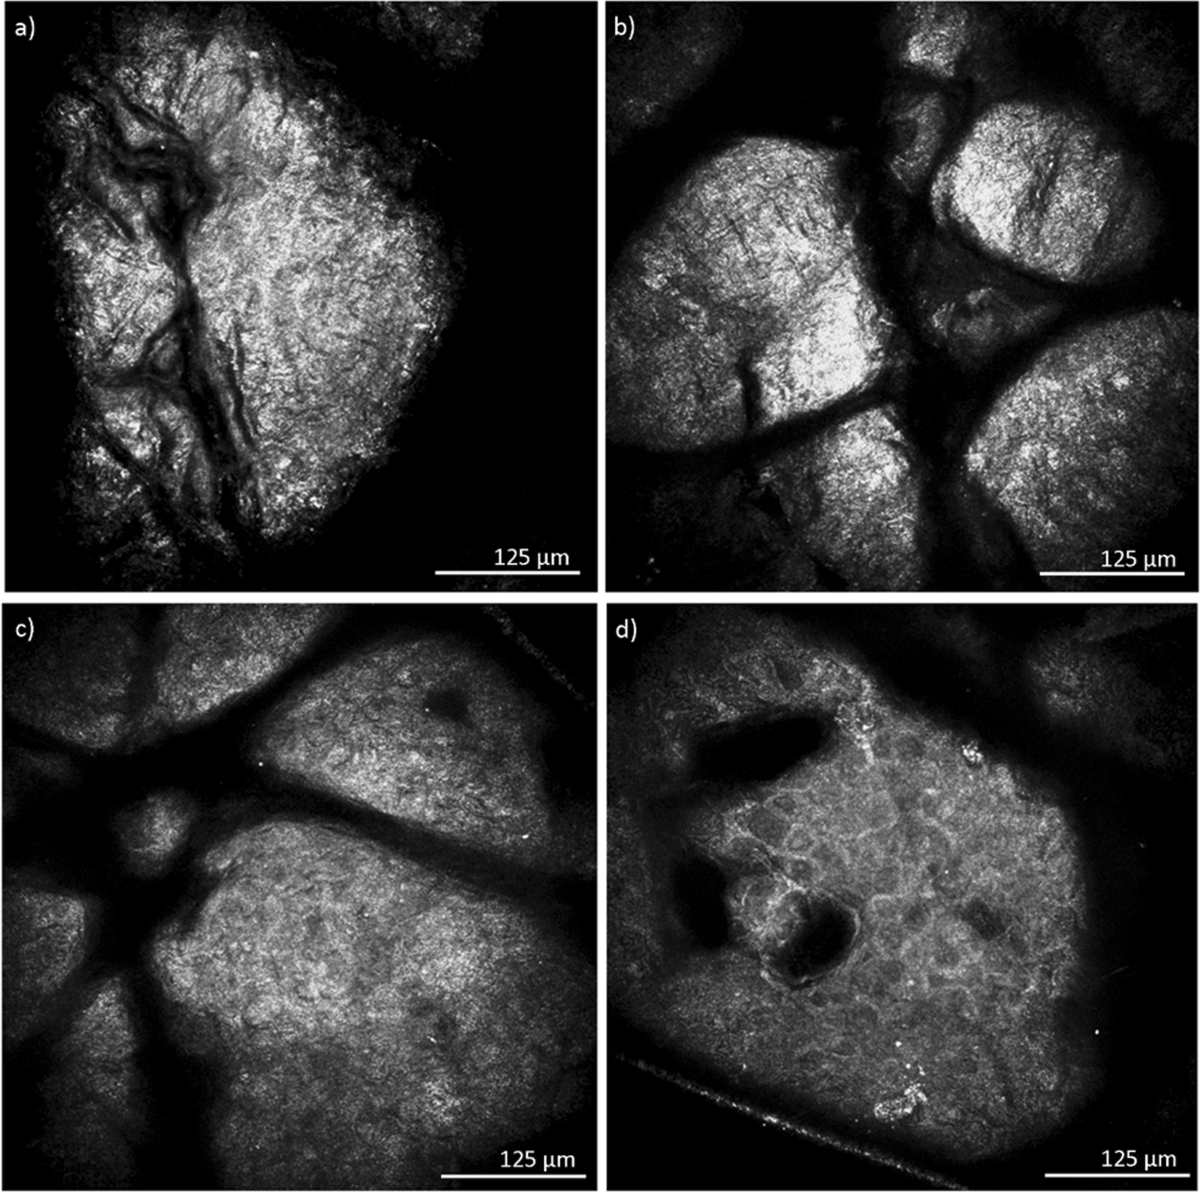

Bring lab-level skin insights directly into your hands.

We combine innovative testing technology with real data to help you decode your skin, track changes, and build routines based on science.

Invented in 2002 by Damon Borich, MD, and his team of engineers, PhD scientists, and healthcare professionals. Our team has worked in the diagnostic field across medical, food, and veterinary monitoring. Now, we’re applying that proven expertise to skincare—giving you real data, real understanding, and real results.